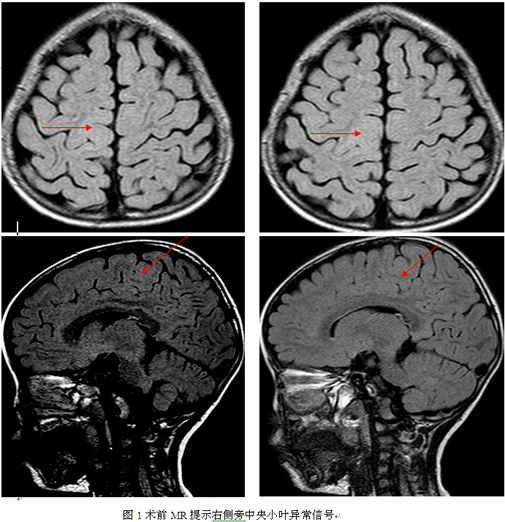

患者陈某,女,3岁,右利手,因发作性肢体抽搐2年余入院。患者入院前每天发作20余次,主要表现为左下肢强直阵挛,曾服用多种抗癫痫药物治疗,发作无任何减轻并出现左下肢肌力进行性下降,符合药物难治性癫痫。入院时查体:左下肢肌力二级,站立不能。入院后行视频脑电图提示:异常脑电图III(清醒/睡眠):间歇期:1、阵发性慢波增多,弥漫性;2、癫痫样放电,弥漫性,中线区著;发作期:临床:左下肢强直→BATS(左著)→左下肢强直-阵挛;EEG:发作型,中线区著;头颅MRI检查提示右侧旁中央小叶异常信号,病灶环绕中央沟生长,考虑局灶性皮层发育不良(见图1)。PET:右侧旁中央小叶、中央区低代谢(见图2)。入院诊断:1、症状性癫痫;2、右侧旁中央小叶异常信号。